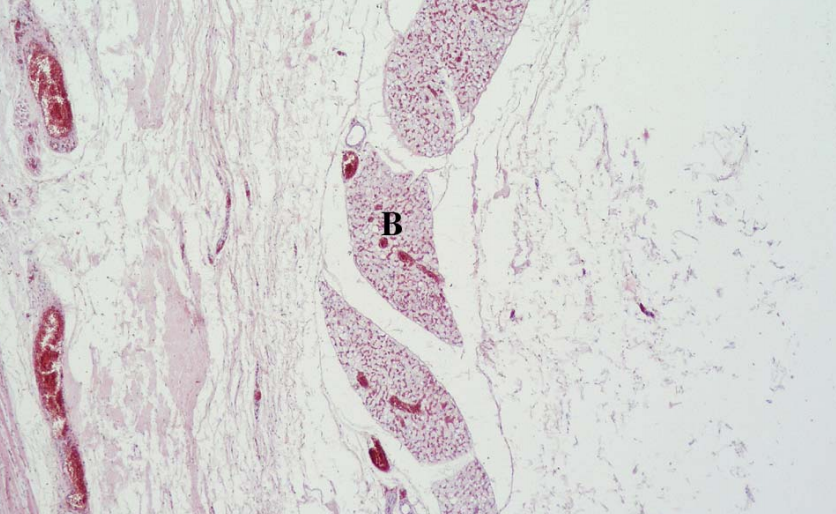

what slide is this?

what connective tissues are present

what muscle tissues are present

what is the endomysin made of? the perimysein?

musculotendon junction

tendon: dense regular CT

skeletal muscle

multinucleated, cross striations

endomysein: reticular fibers

perimyseins: loose CT